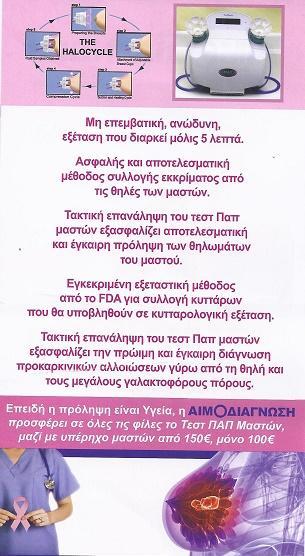

Μικροβιολογικό εργαστήριο Καπανδρίτι, τεστ παπ μαστού, τεστ τροφικής δυσανεξίας Καπανδρίτι